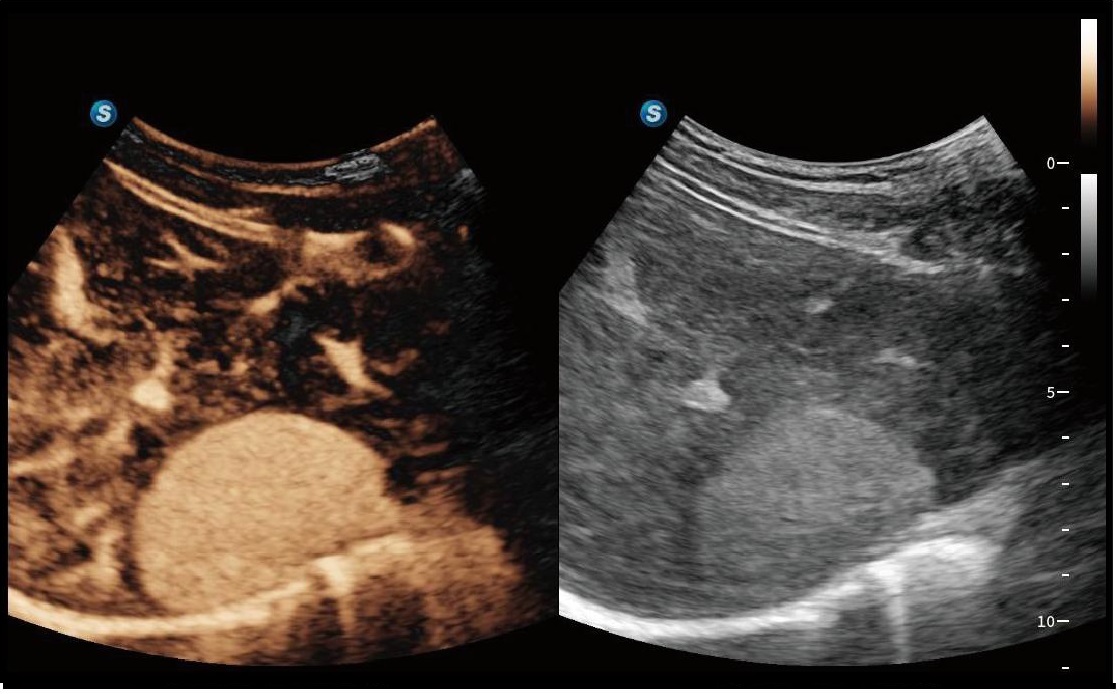

SWE

S-SWE (Shear Wave Elastography), karaciğer fibrozisinin kantitatif değerlendirmesini mümkün kılar ve klinik tanı güvenini artırmak için bir kalite haritası görüntüler.